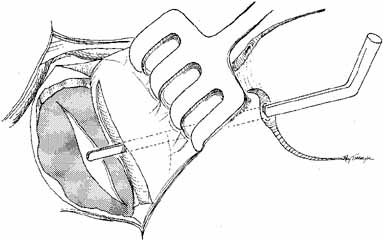

should be applied for 12 to 24 hours.  Fig. 45 The anterior flaps of the lacrimal sac and nasal mucosa are closed with

interrupted absorbable sutures. The periosteum is closed in a similar

fashion. A Silastic catheter and nasal packing can be used to separate

the anterior and posterior flaps, but the Silastic tubing with the cuff

in place has advantages; it can remain in place almost indefinitely

in an adult, and it is cosmetically invisible. Fig. 45 The anterior flaps of the lacrimal sac and nasal mucosa are closed with

interrupted absorbable sutures. The periosteum is closed in a similar

fashion. A Silastic catheter and nasal packing can be used to separate

the anterior and posterior flaps, but the Silastic tubing with the cuff

in place has advantages; it can remain in place almost indefinitely

in an adult, and it is cosmetically invisible.

Fig. 46 The orbicularis muscle and subcutaneous tissues are closed with interrupted 6–0 absorbable

sutures. The skin is closed with a running subcuticular

suture of 5–0 nylon. Fig. 46 The orbicularis muscle and subcutaneous tissues are closed with interrupted 6–0 absorbable

sutures. The skin is closed with a running subcuticular

suture of 5–0 nylon.